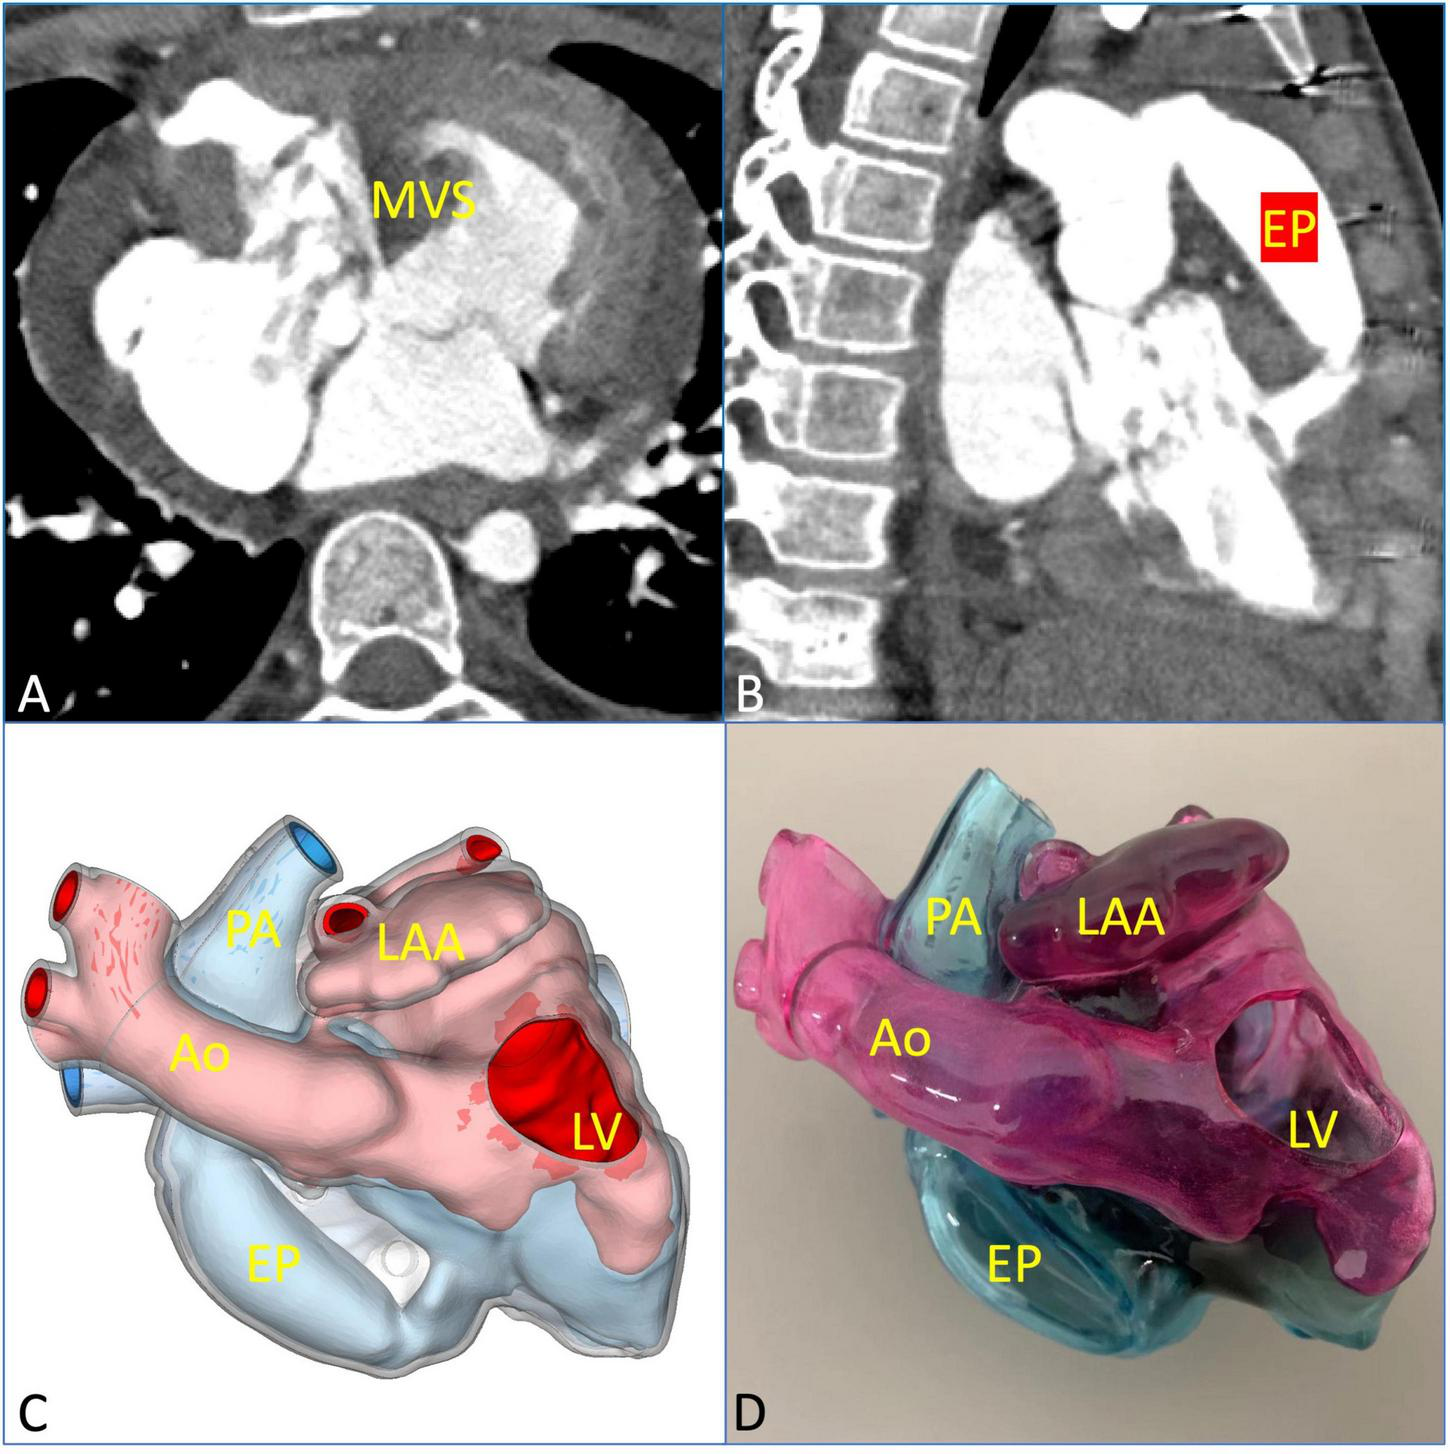

Digital imaging and communication of medicine (DICOM) format of the patient CTA data was imported into Materialize Mimics version 21.0 (Leuven, Belgium), and the 3D reconstructed model was segmented using the threshold segmentation function (Figure 2A). Then, the acquired 3D reconstructed model of the heart was digitally removed, trimmed, smoothened, and repaired in Materialize 3-matic (Leuven, Belgium) to restore the complete anatomical structures of the heart (Figure 2B). Standard tessellation language (STL) file of 3D reconstruction was exported to Stratasys Polyjet 850 multi-material full-color 3D printer (Figures 2C, E). The digital acrylonitrile butadiene styrene was used to print the model, different anatomical structures were matched with different colors, and then the 3D printed whole-heart model was obtained (Figures 2D, F).

FIGURE 2

Reconstructed process of three-dimensional (3D) printed model and preoperative evaluation. (A) Original computed tomography angiography data. (B) Edition of the mask. (C,D) The 3D reconstructed and printed models are shown in the front view, respectively. (E,F) The 3D reconstructed and printed models are shown in the rearview, respectively. In the 3D printed model, the red part is the aorta (Ao), the blue part is the pulmonary artery (PA), the yellow part is the left atrial appendage (LAA), the pink part is the left atrium (LA) and left ventricle (LV), and the light blue part is right atrium (RA) and right ventricle (RV).

According to the 3D printed model, surgeons may intuitively understand the specific anatomical structures and adjacent relationships of the heart. In addition, the diameter and length of the extracardiac pipe required during the operation may be measured on the model, so as to plan the operation more accurately and effectively. After a comprehensive evaluation, the team decided to perform surgical repair of physiological correction.

A midsternal incision was made, and aorta-superior and inferior vena cava cardiopulmonary bypass was established. The small right ventricle was revealed with obvious stenosis of the right ventricular outflow tract (RVOT) and PV. MVSA was formed, and the aneurysm presented like protrusion to RVOT (Figure 3A). The stenosis was aggravated during systole without ventricular septal defect, and the tricuspid valve (TV) was parallel to RVOT and well developed. MVSA was removed, and the residual membranous part of the interventricular septum was directly stitched (Figure 3B). The anterior leaflet of the TV was sutured with a spacer, and ASD was repaired with a patch. Due to the special adjacent relationships of PV, the connection between the right ventricle and pulmonary artery was established by using the extracardiac pipe technique. The pipe was made by a bovine pericardial patch with a diameter close to that of the aorta. The method was as follows: Three leaflets of the same size were cut and sewn parallel to the bovine pericardial patch. Then, the bovine pericardial patch was rolled into the tube shape and sutured to form a self-made pipe, which was used in RVOT reconstruction (Figures 3C, D). After the pipe reconnected, the heart returned to the sinus rhythm. The patient recovered well after the operation, and cyanosis disappeared before discharge. There was no residual regurgitation in the atrial septum and only mild TR. The residual membranous part of the interventricular septum was positioned well (Figure 4A). The extracardiac pipe was well-functioning without regurgitation or stenosis (Figure 4B). The postoperative 3D reconstructed and printed model showed the morphology of the anatomical structures, indicating that the operation achieved good results (Figures 4C, D).

FIGURE 4

Postoperative evaluation using multimodal imaging verified the curative effect of the surgical repair. (A) The residual membranous part of the interventricular septum was in a good position and well-functioning. (B) The extracardiac pipe functioned well. (C,D) The postoperative 3D printed model was observed clearly to verify the effect of the operation. EP, extracardiac pipe.